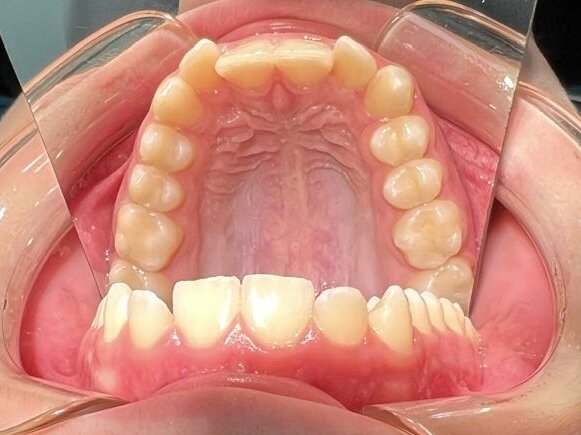

Наши работы

Реальные результаты лечения наших пациентов. Все фото сделаны в нашей клинике с согласия пациентов.

Исправление прикуса

Хирургическое раскрытие ретинированных зубов

Лечение кариеса и реставрация

Реставрация зубов